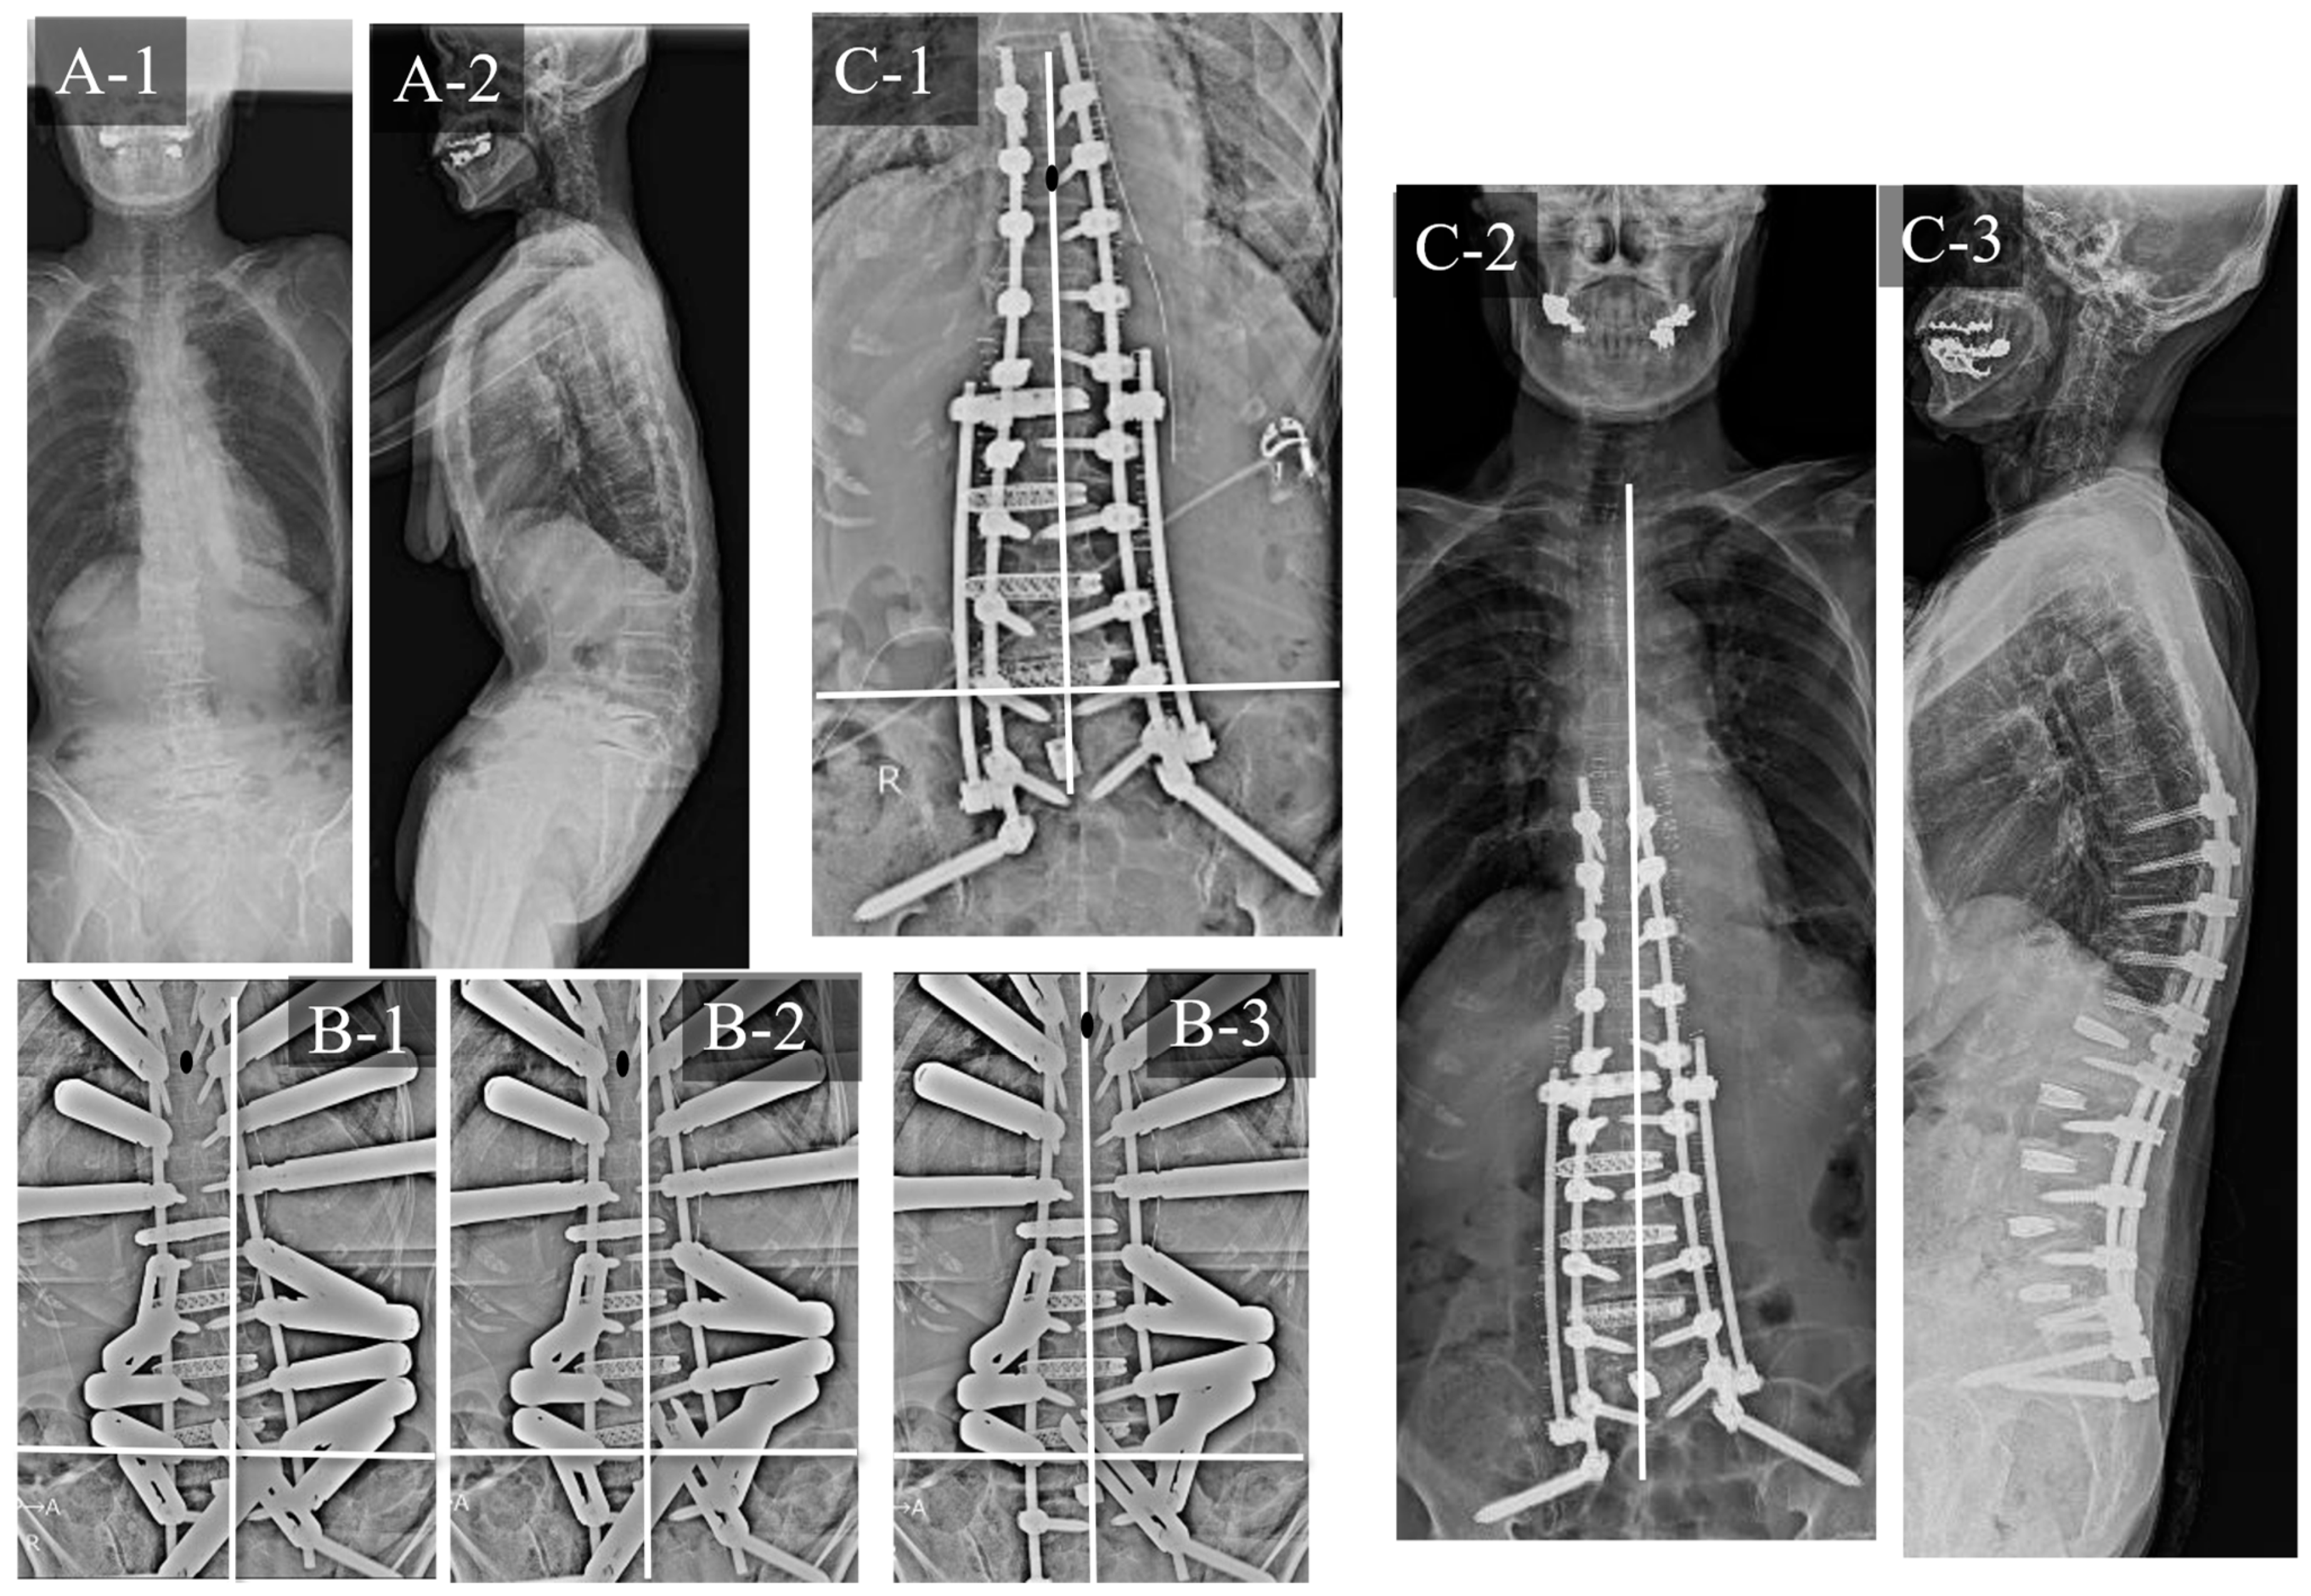

3.2. Case Study 2: RR and SD